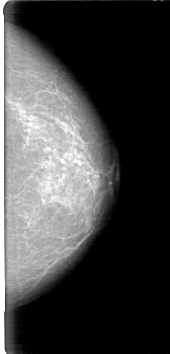

D_4027_1.RIGHT_CC

RIGHT_CC LINES 5251 PIXELS_PER_LINE 2251 BITS_PER_PIXEL 12 RESOLUTION 43.5 OVERLAY